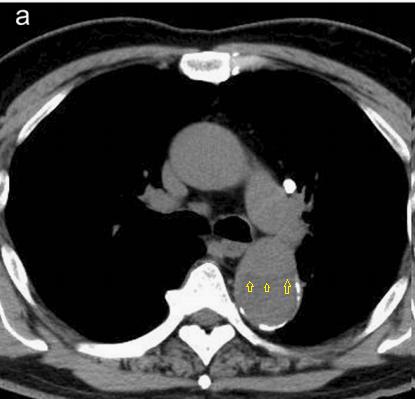

下图的胸部CT平扫,有什么致命的问题?

图7

仔细一看,主动脉里面有线样阴影!并且,线样阴影两边的密度一高一低!

图8

增强CT一看,主动脉夹层,密度相对高的是流动的血液!

图9